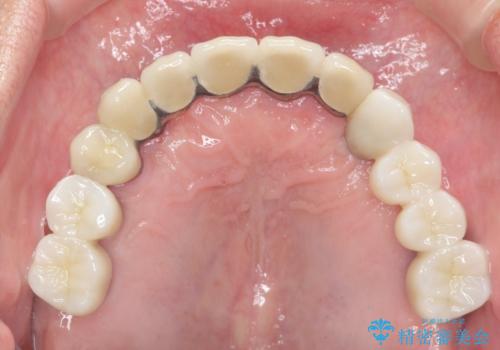

上顎は、残っている前歯も揺れがあり残すためにはクラウンでつなぐ歯周補綴が必要な状態です。

また咬合負担に不安のある前歯を助けるためにも、臼歯部にインプラント補綴を行いしっかりとかめる状態とすることも大切です。